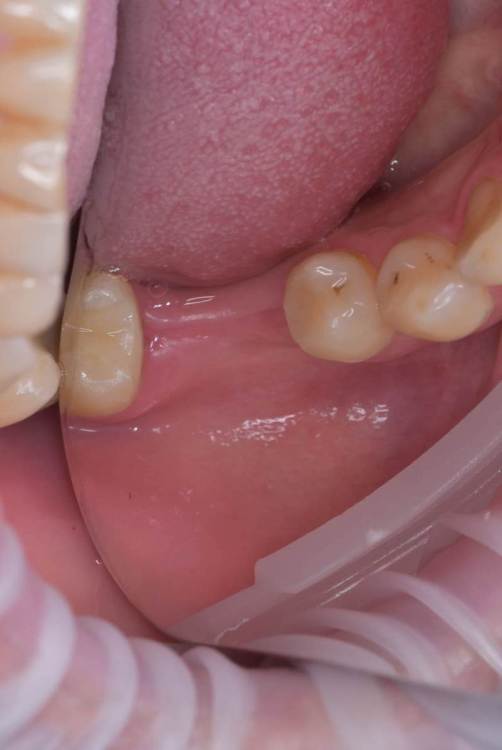

Irouil Опубликовано 15 июля, 2023 Поделиться Опубликовано 15 июля, 2023 Интересно, одномоментно в лунку дистального корня не зашло бы? Предположу, что либо ангуляция вышла бы экстремальной, либо слишком близко к вестибулярной стенке пришлось бы ставить Вообще, эти случаи с выраженным поднутрением в боковых отделах нижней челюсти достаточно коварные, на мой взгляд, с точки зрения позиционирования 1 Ссылка на комментарий

TIGER Опубликовано 15 июля, 2023 Автор Поделиться Опубликовано 15 июля, 2023 @Irouil было бы сложно стабилизировать в этих условиях,в случае неуда ситуация усугблялась,решил пойти по пути сохранения тканей,дал организму самому регенирировать,при имплантации добавил чуть тканей @Doc ещё Миш писал в книге о минусах имплантации семёрок кстати 1 Ссылка на комментарий